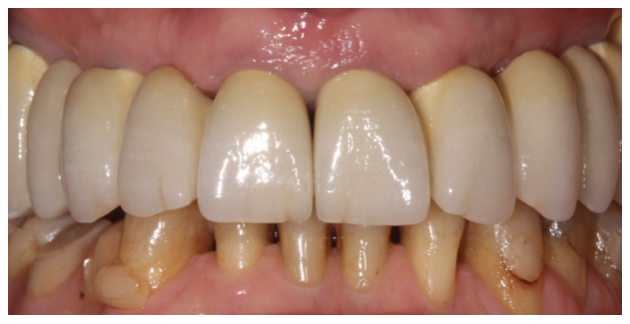

Bridge provisoire en place avec un rendu esthétique satisfaisant :

Détail de la fausse gencive du bridge provisoire en bouche :

Aspects esthétiques à 4 mois :

Pour mémoire cas au départ :